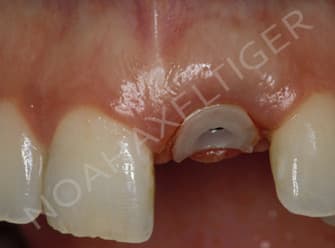

Un pilier de cicatrisation customisé ou personnalisé c'est une vis de ciatrisation individualisée : elle peut être faite de plusieurs facons par exemple à partir de ton porte implant que tu modifies par apport successif de composite.

Ca ressemble à cela :